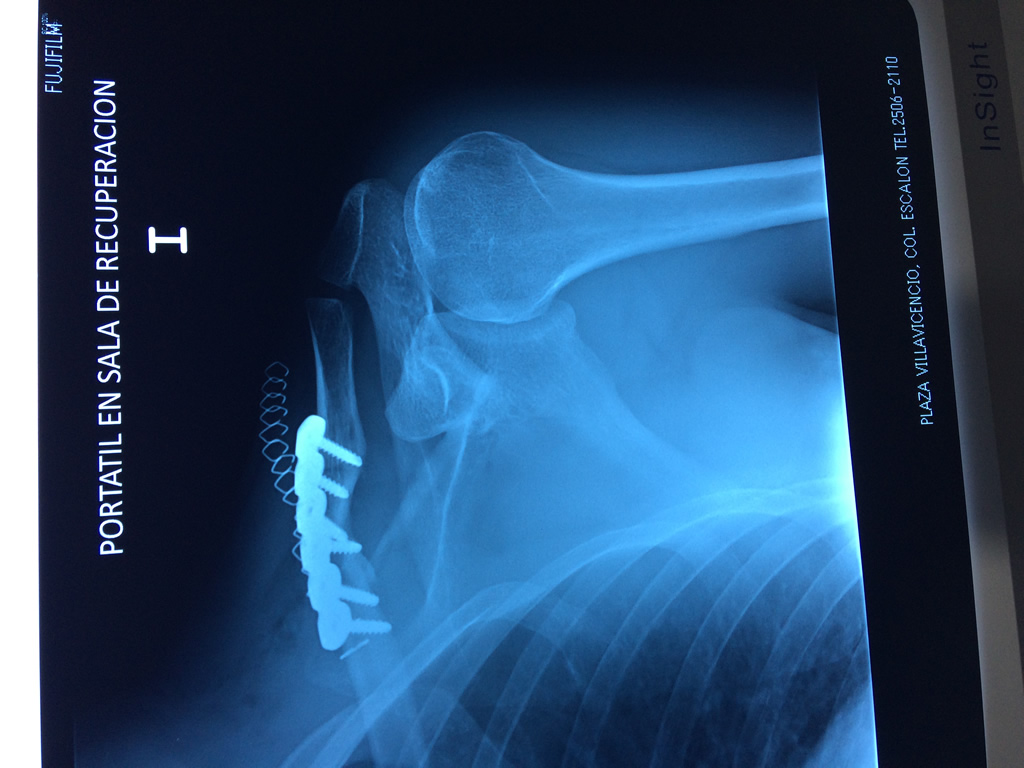

Clavícula

La clavícula es un hueso largo, con forma de "S" itálica, situado en la parte anterosuperior del tórax. Junto con la escápula forman la cintura escapular. Se puede palpar por toda su longitud y se extiende del esternón al acromion de la escápula, siguiendo una dirección oblicua lateral y posterior.

Se considera el único medio de unión entre el miembro superior y el tórax. A pesar de su aspecto, similar al de un hueso largo, posee una estructura semejante a la de un hueso plano, ya que carece de epífisis y de diáfisis, lo que la harían entrar dentro de la clasificación de hueso largo. Carece de un canal medular propiamente dicho.